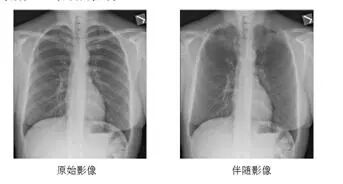

3.体检专用套件:DRX-Compass X针对这一特殊领域配置了尘肺病检查模式,从摄影条件、图像处理方式按照相关国家标准设置,从而可以提供符合规范的标准数字化X射线影像;系统配置了Bone suppression software 骨抑制成像软件,可通过软件后处理去除胸部前后位及后前位的后肋及锁骨显示,帮助医生更清楚的在体检阅片过程中识别肺部软组织病变如肺结节、气胸等。